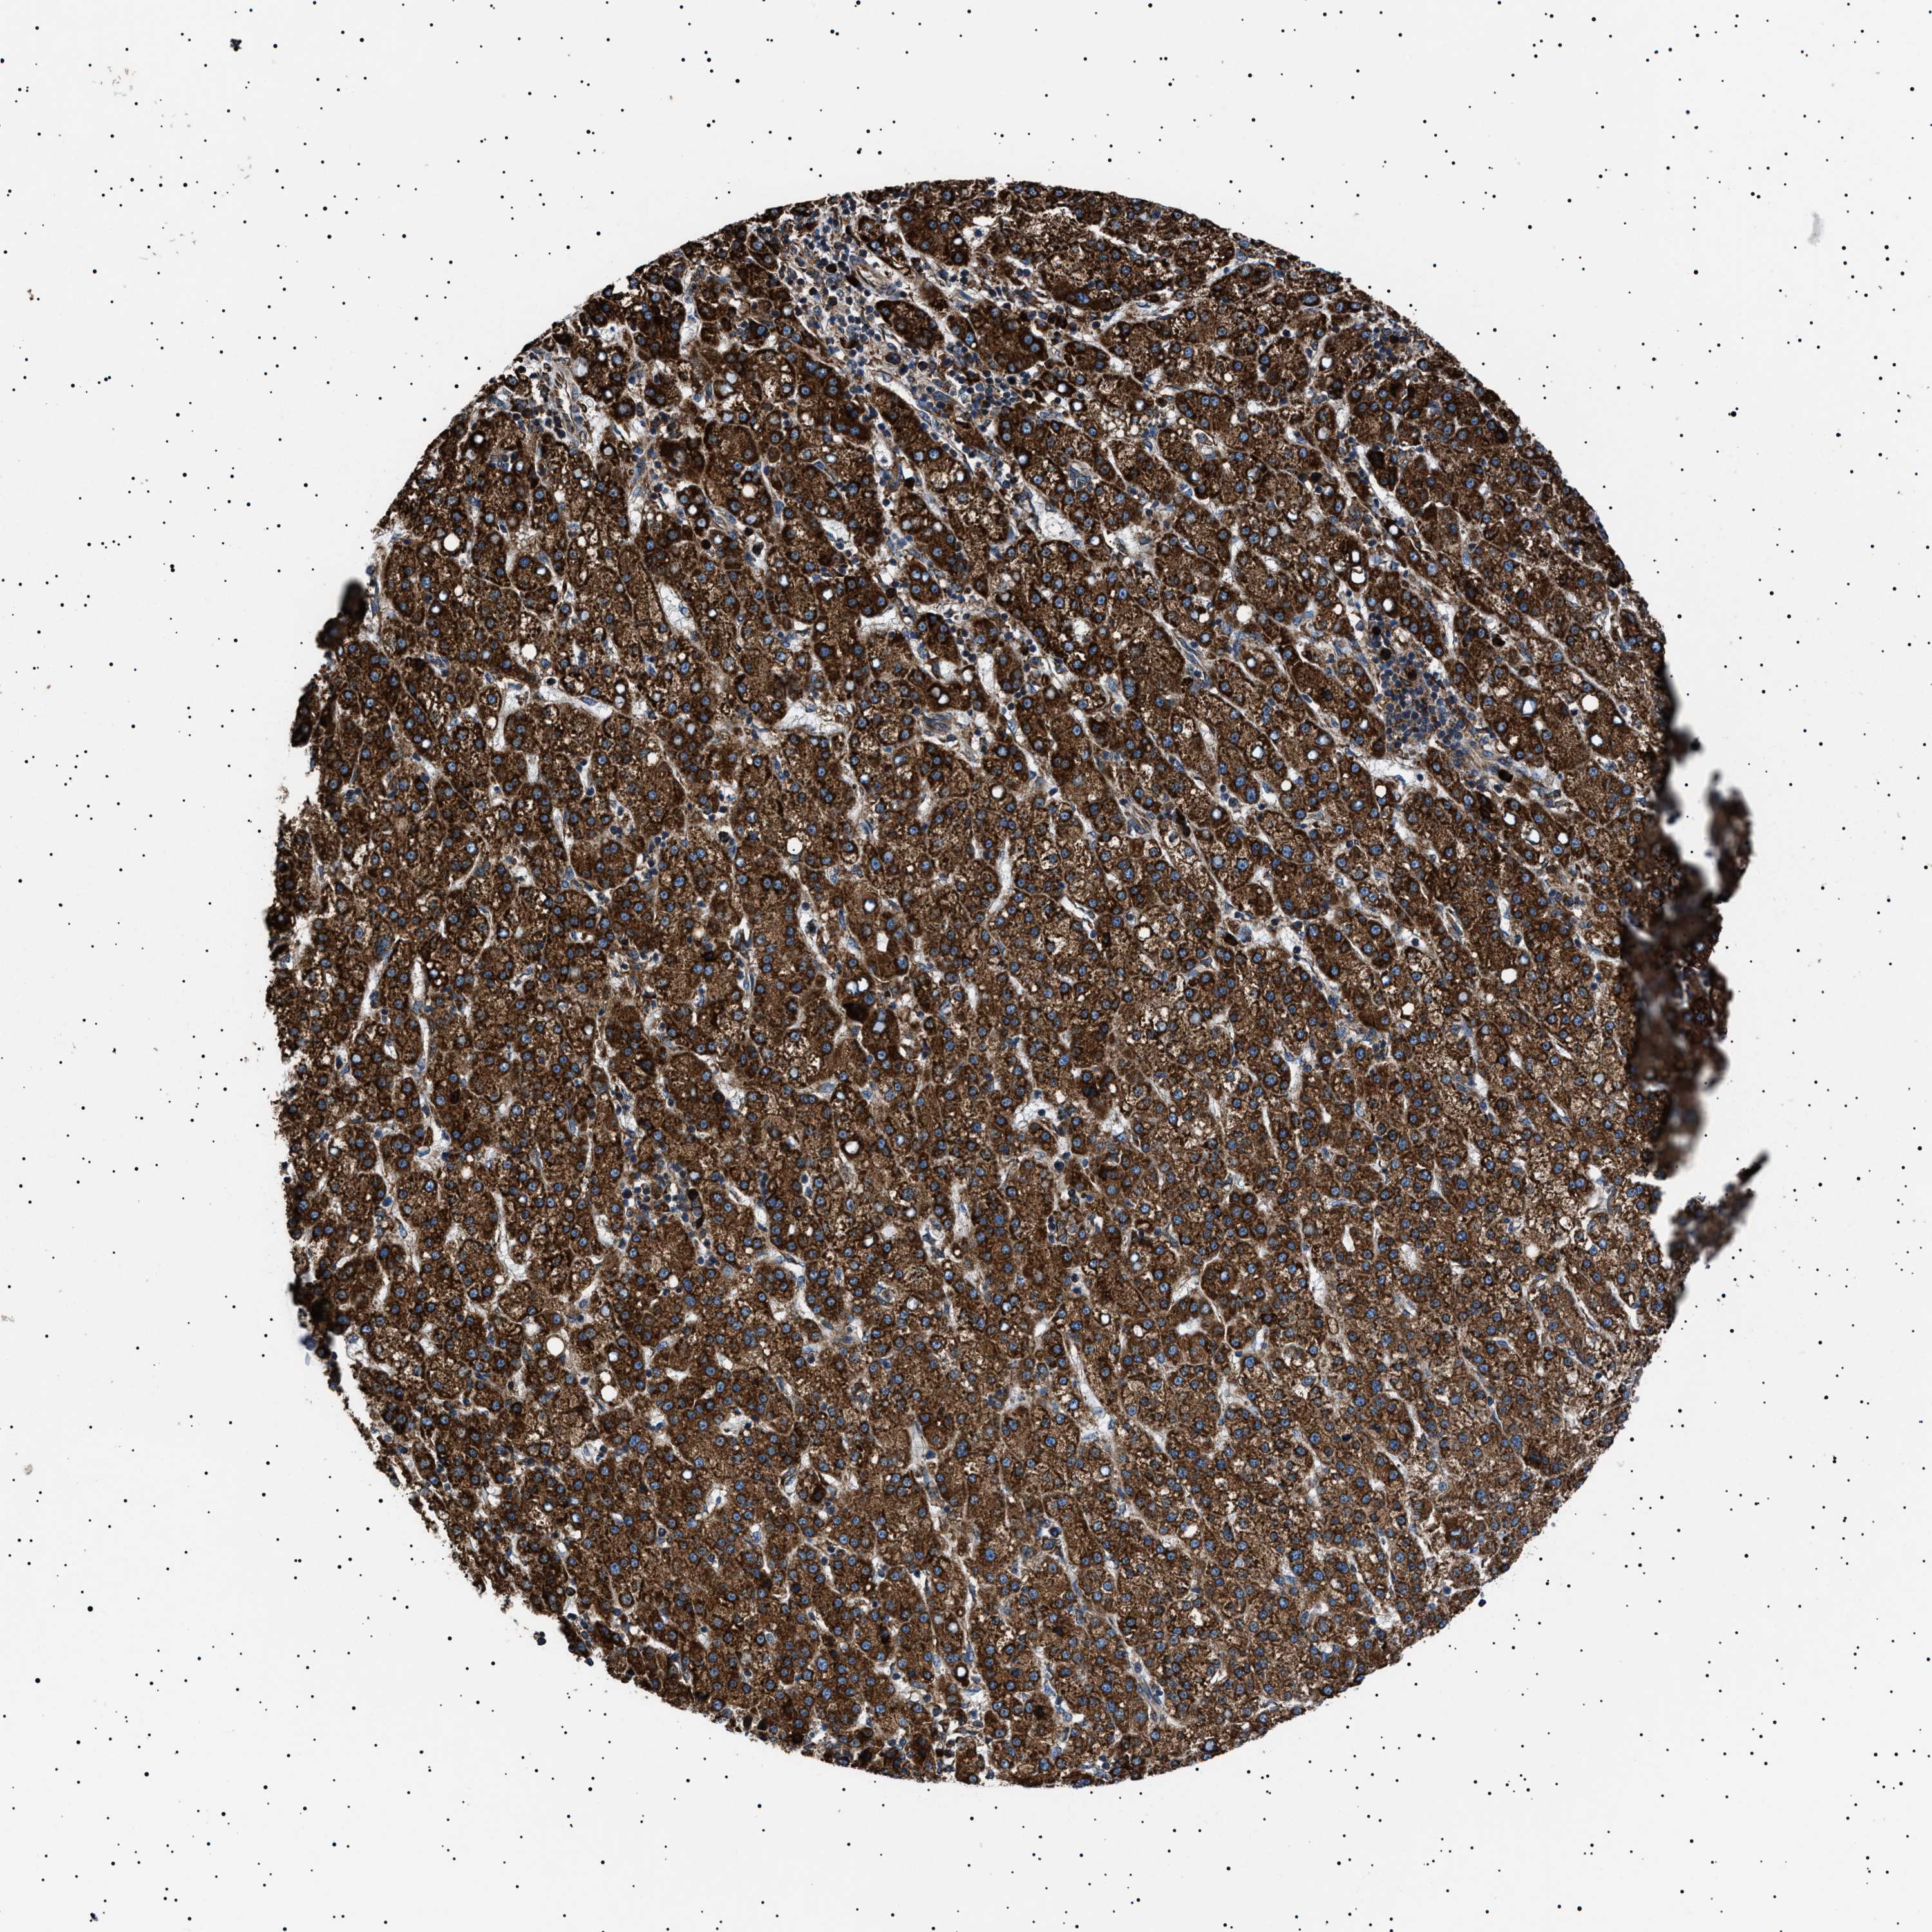

LIVER CANCER - Protein expressioni

A mouse-over function shows sample information and annotation data. Click on an image to view it in a full screen mode. Samples can be filtered based on level of antibody staining by selecting one or several of the following categories: high, medium, low and not detected. The assay and annotation is described here.

Note that samples used for immunohistochemistry by the Human Protein Atlas do not correspond to samples in the TCGA dataset.

Antibody stainingi

Antibody staining in the annotated cell types in the current human tissue is reported as not detected, low, medium, or high, based on conventional immunohistochemistry profiling in selected tissues. This score is based on the combination of the staining intensity and fraction of stained cells.

Each image is clickable and will lead to virtual microscopy that enables deeper exploration of all samples and also displays staining intensity scores, fraction scores and subcellular localization as well as patient and tissue information for each sample.

Antibody HPA001915

Antibody HPA021542

Staining

High

Medium

Low

Not detected

Intensity

Strong

Moderate

Weak

Negative

Quantity

>75%

75%-25%

<25%

None

Location

Nuclear

Cytoplasmic/membranous

Cytoplasmic/membranous,nuclear

Cholangiocarcinoma

Carcinoma, Hepatocellular, NOS